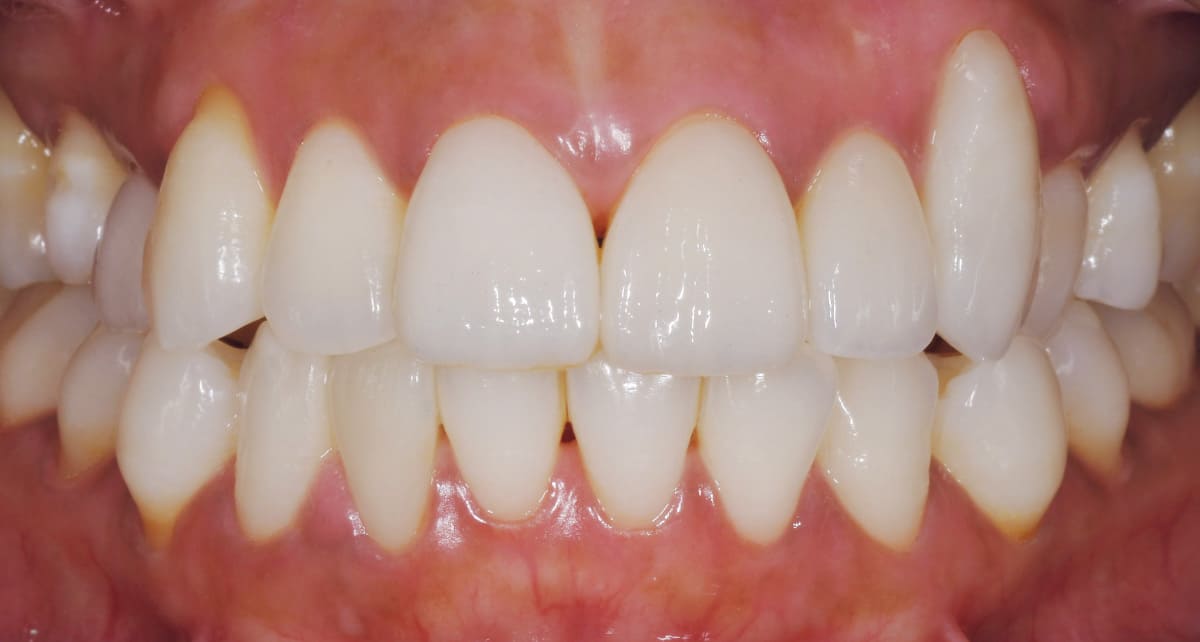

セラミック|費用はかかるが仕上がりの良さは抜群。

Before

After

よりきれいな仕上がりを目指すのであれば、やはりセラミックがファーストチョイス。透明感があり、自然歯と変わらない白さが望めるからだ。ジルコニアよりコストがかかるので、前歯はセラミック、奥歯はジルコニアという選択も。

【料金】15万円〜

【治療期間】1週間〜3週間程度

(特別な機材がある病院ではワンデイ治療が可能)